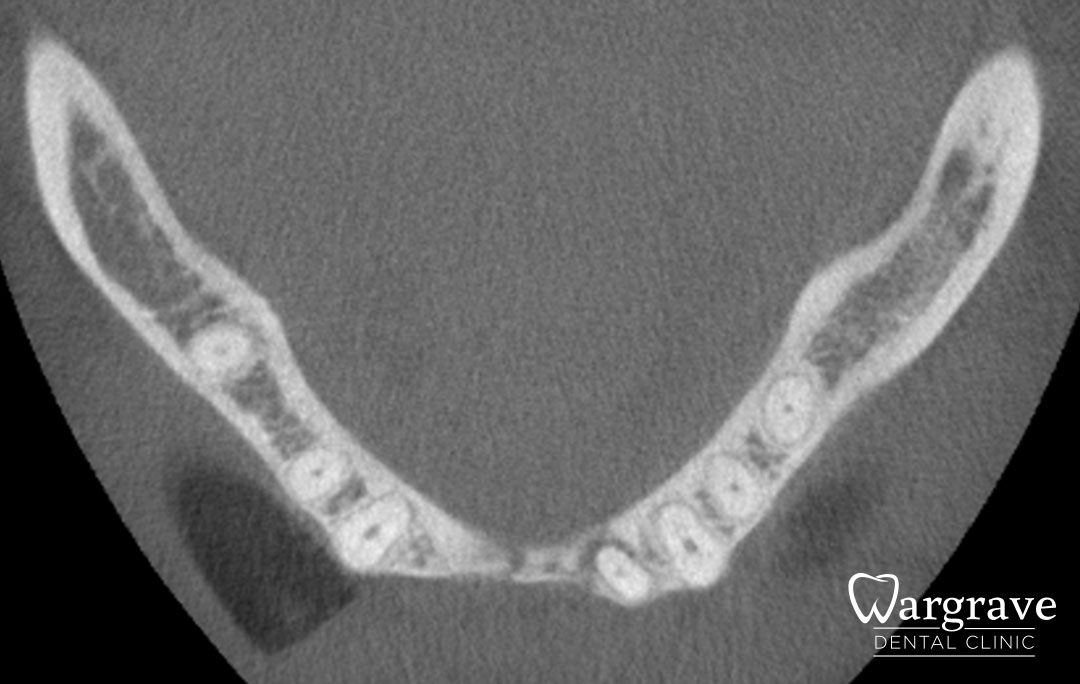

Anterior Mandible Bone Regeneration

Before

This patient presented with a very narrow anterior mandible and insufficient bony width for dental implants. An extensive grafting procedure was carried out. Several months later the site was restored with a four unit fixed Implant Bridge on two implants